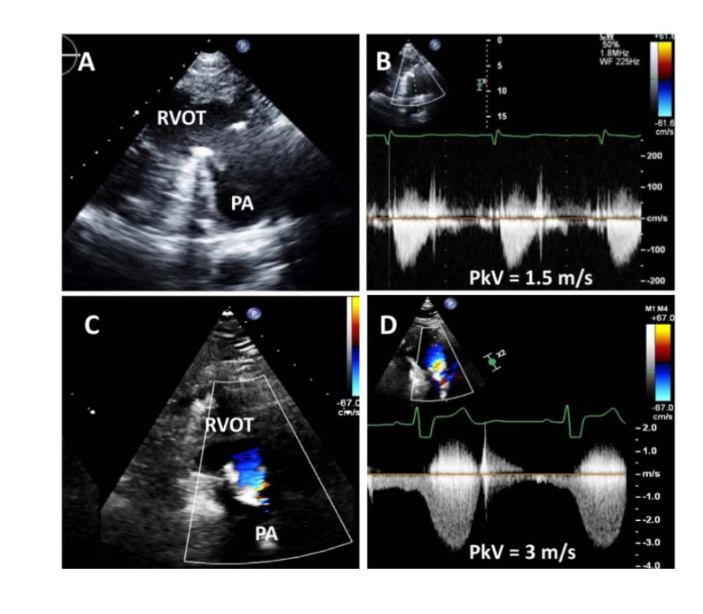

Prosthetic Pulmonary Valves

when evaluating the severity of prosthetic stenosis, that what flow velocities

may be encountered in locations other than the prosthetic valve?

what stenosis may also be present

when evaluating the severity of prosthetic stenosis, that high flow velocities

may be encountered in locations other than the prosthetic valve

Branch vessel stenosis or conduit edge stenosis may also be present

Echocardiographic assessment of valve obstruction should include what 5 things

what about the prosthesis

observaation of qualitative indicators of what

quantitation of severity of what

any changes from what assessments in…

what does using the jet of TR determine?

Type and size of prosthesis

Observation of qualitative indicators of obstruction (e.g., thrombus, pannus)

Quantitation of severity of stenosis

Any changes from previous assessments in serial examinations

RV systolic pressure should be determined using the jet of TR

Prosthetic valve failure or dysfunction predominantly manifests as what?

Prosthetic valve failure or dysfunction predominantly manifests as stenosis

rather than regurgitation

Identifying the location of stenosis is important

Obstruction may occur further along a what rather than at where?

what Doppler is helpful in determining the precise location of obstruction

Quantitative parameters are generally limited to what two things

Obstruction may occur further along a conduit or in the PA rather than at the

valve

PW Doppler is helpful in determining the precise location of obstruction

Quantitative parameters are generally limited to peak velocity and mean

gradient

Prosthetic Aortic Valves what are the views for interrogation

PSAX, PLAX< A3C, A5C

what is the AV peak velocity that stenosis is present

prosthetic Aortic jet velocity > 3 m/s